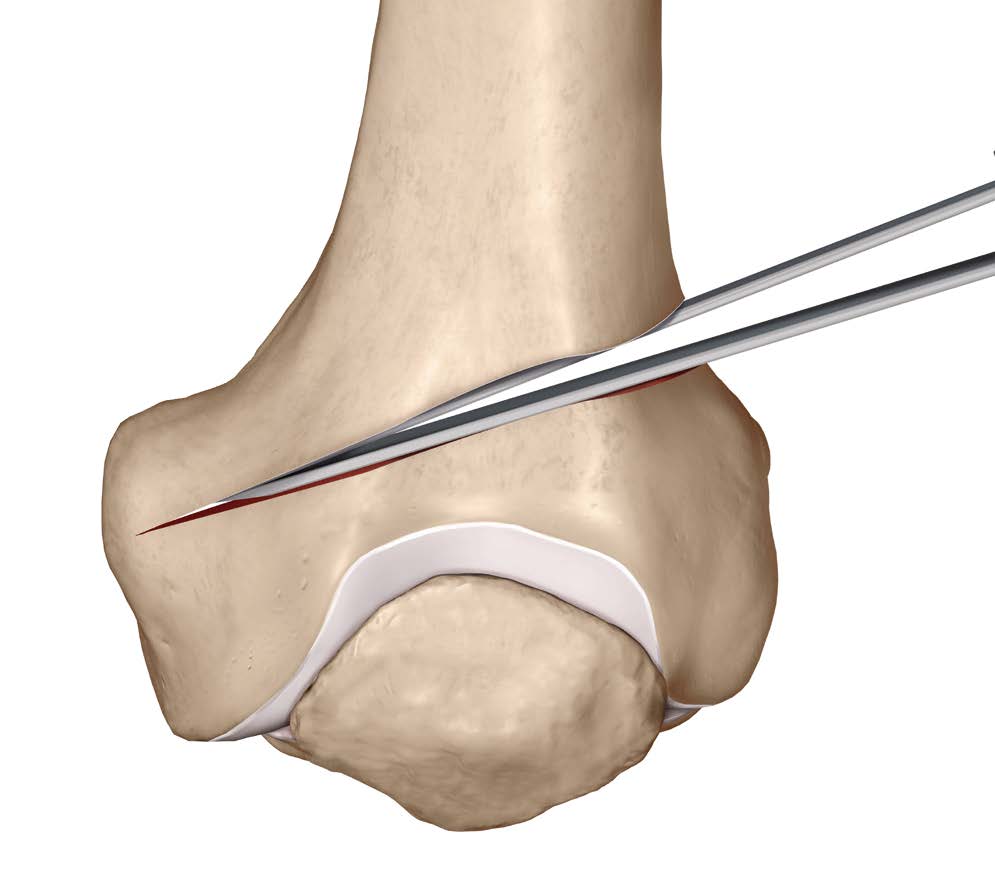

Osteotomy

- insert two K wires for desired wedge

- resect templated wedge

- stop 1 cm short of lateral cortex

- close femoral wedge